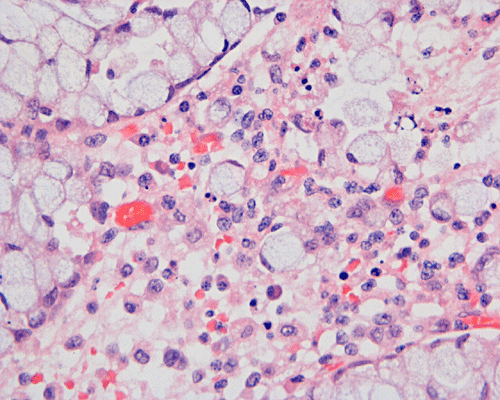

Histopathology: On scanning magnification, the mucosa has a sandwich like structure (Panel A). At the bottom is a layer of partially destroyed glands with a middle layer of mucoid material and topped by a layer of inflammatory exudate (Ž in Panel A). In some areas, the inflammatory exudate takes the shape of a mushroom or volcano (Panel B). The submucosa is edematous but lacks significant inflammatory cell infiltration. The top layer of inflammatory exudate is composed exclusively of degenerated polymorphonuclear leukocytes (Panel C and D). At the base of the mucosa, the outline of the normal glandular architecture is maintained but there is intense infiltration by polymorphonuclear leukocytes in the lamina propria (Panel E and F). On high-magnification, the crypts are filled by signet ring cells. In severely inflammed areas, there are some single singnet ring cells in the lamina propria (Panel G). In the deeper part of the mucosa where inflammation is not as intense, the boundary between the crypts and the lamina is respected by the signet cells (Panel H). In the more superficial part of the mucosa, the glandular architecture is disrupted (Panel I). Sporadic signet ring cells are also found in mucosa that are relatively unaffected (Panel J).